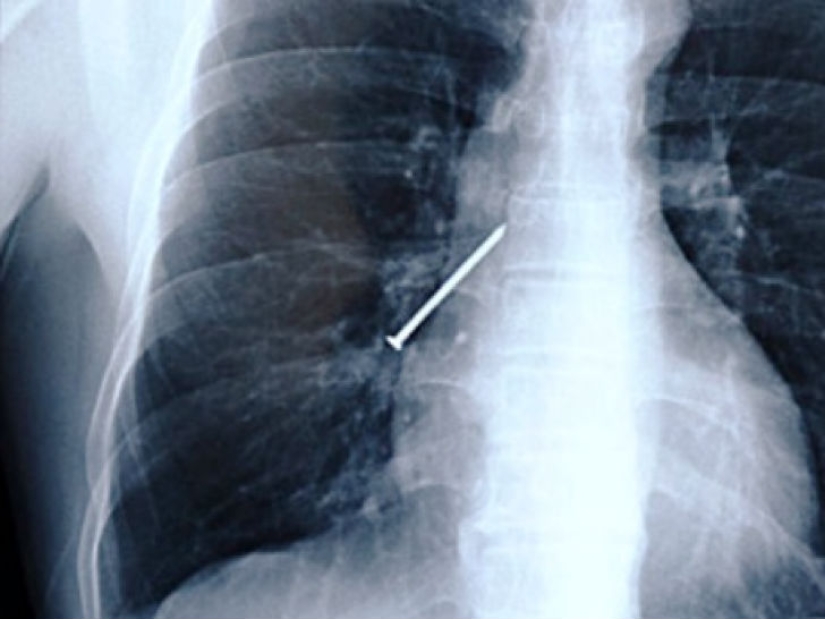

Have you ever held a nail in your teeth when your hands are busy with a hammer? Here is a picture of a man from China who coughed while working.